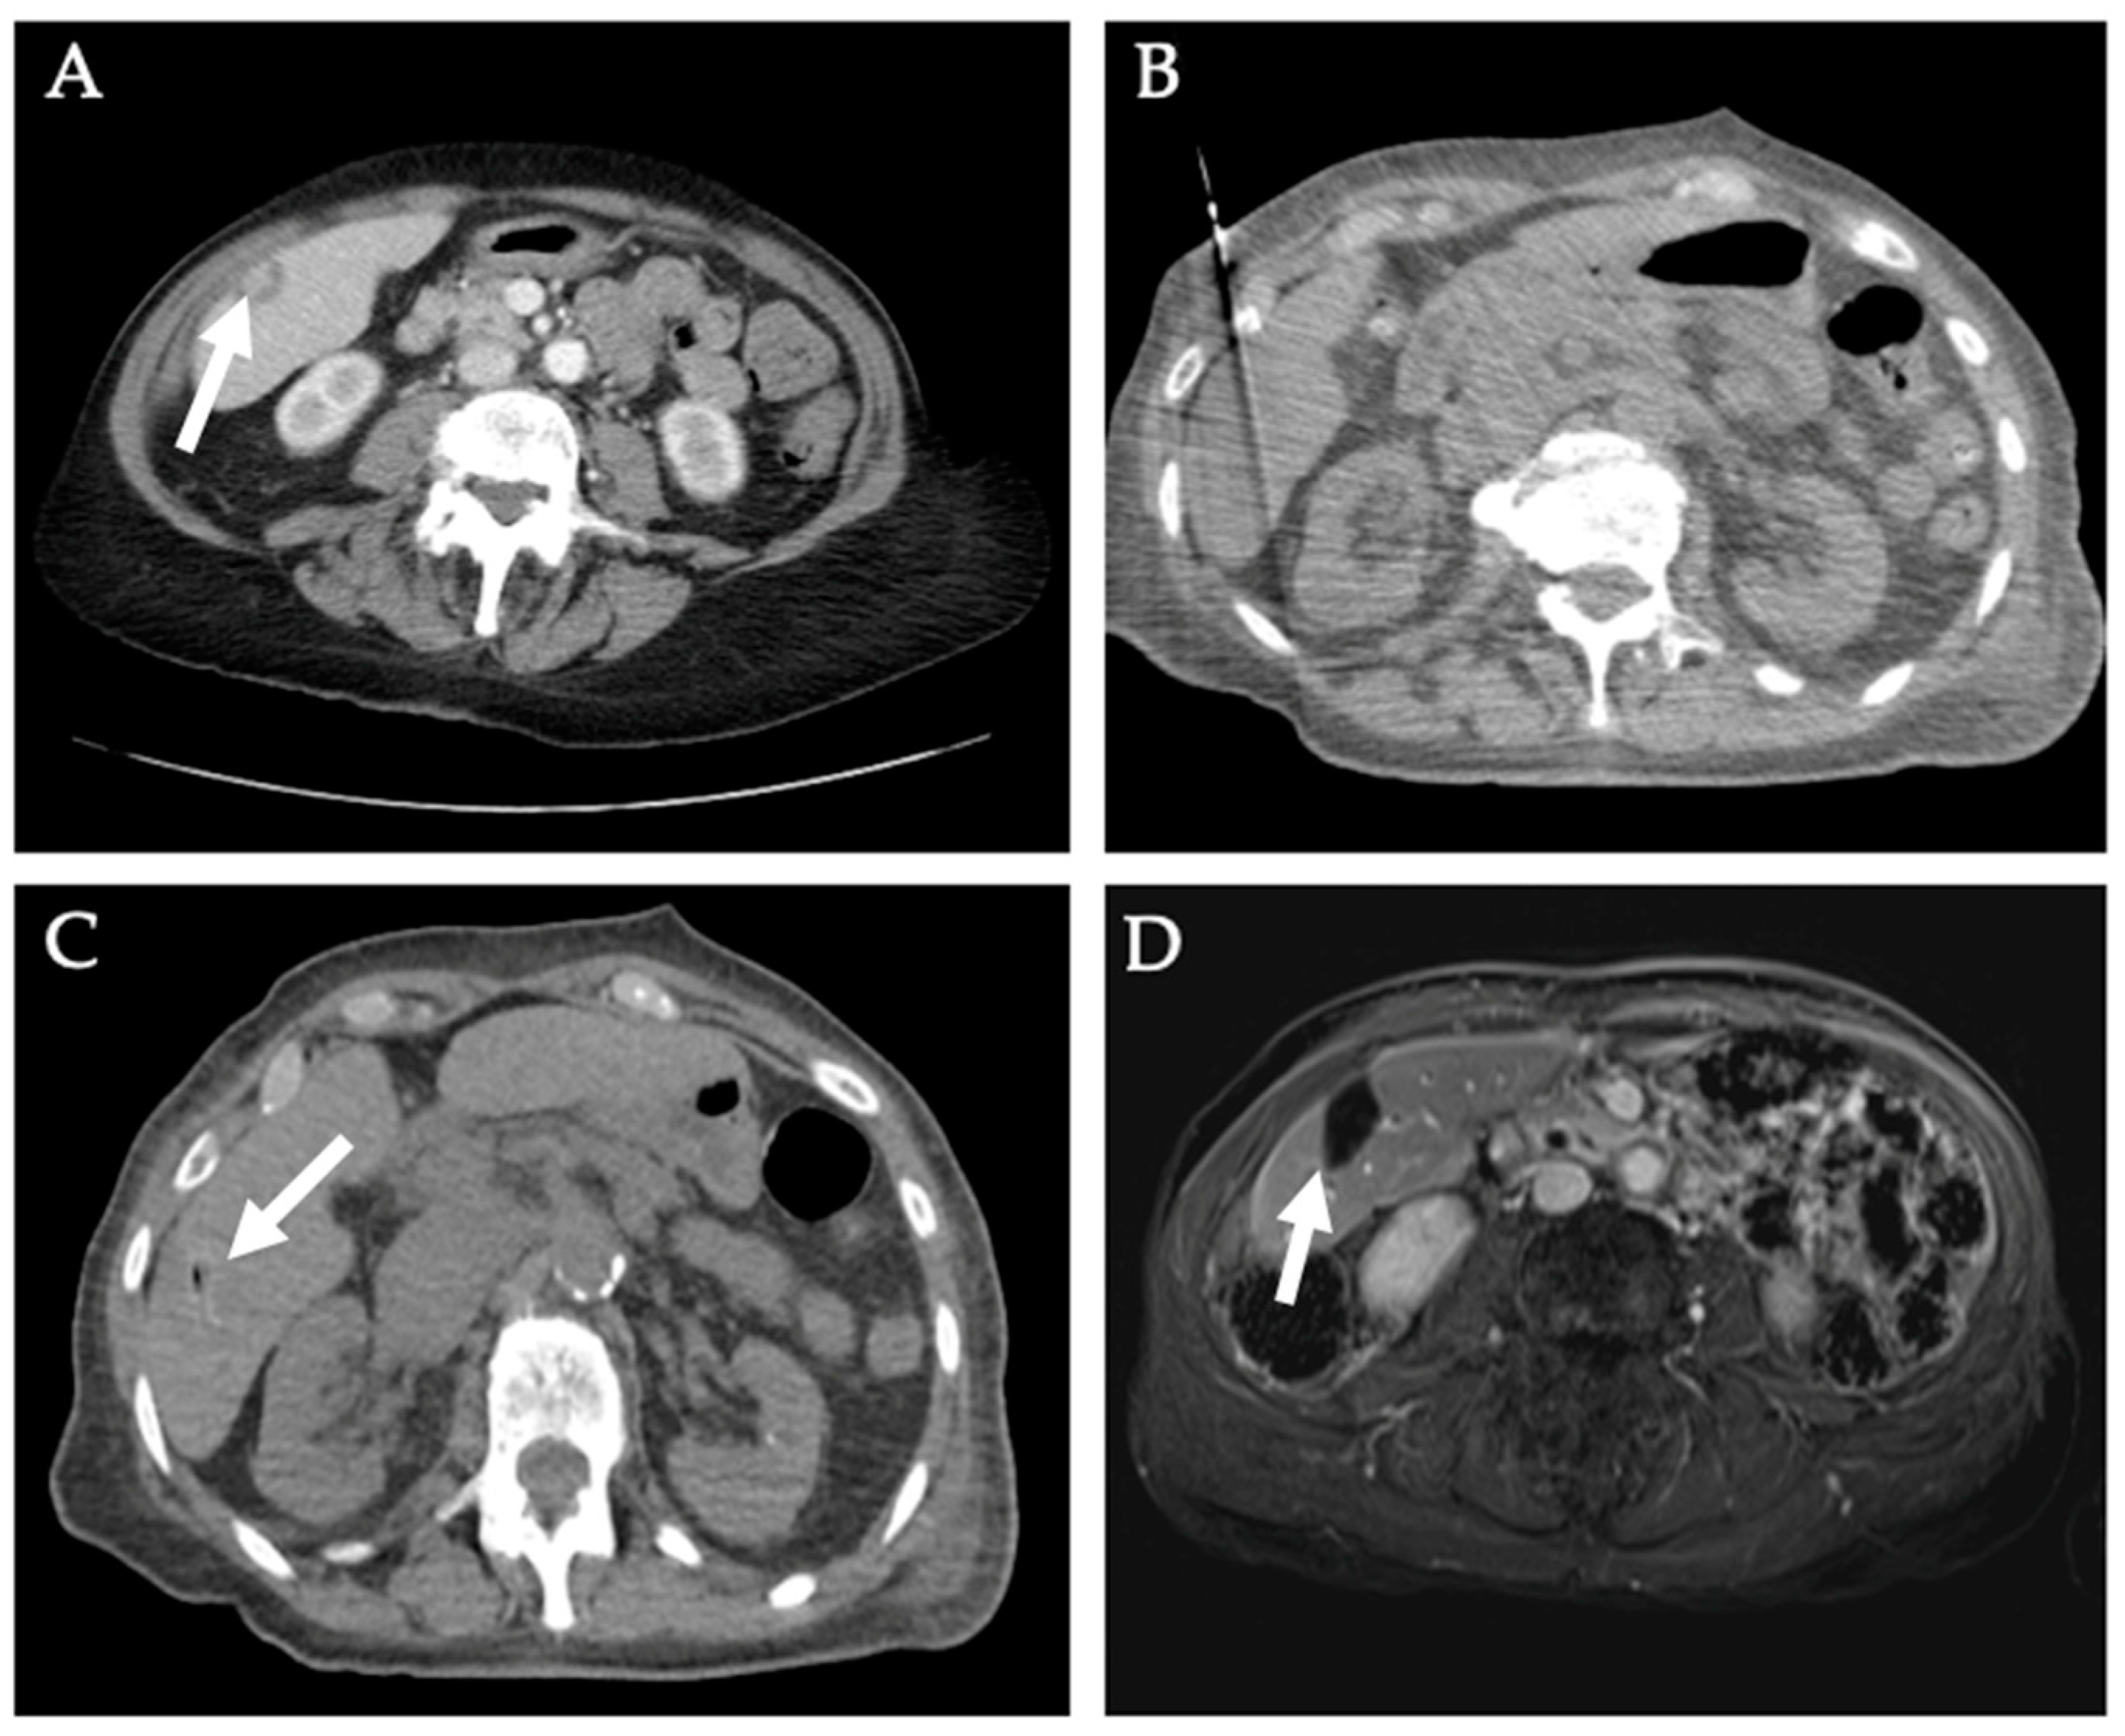

5. Renal Tumors